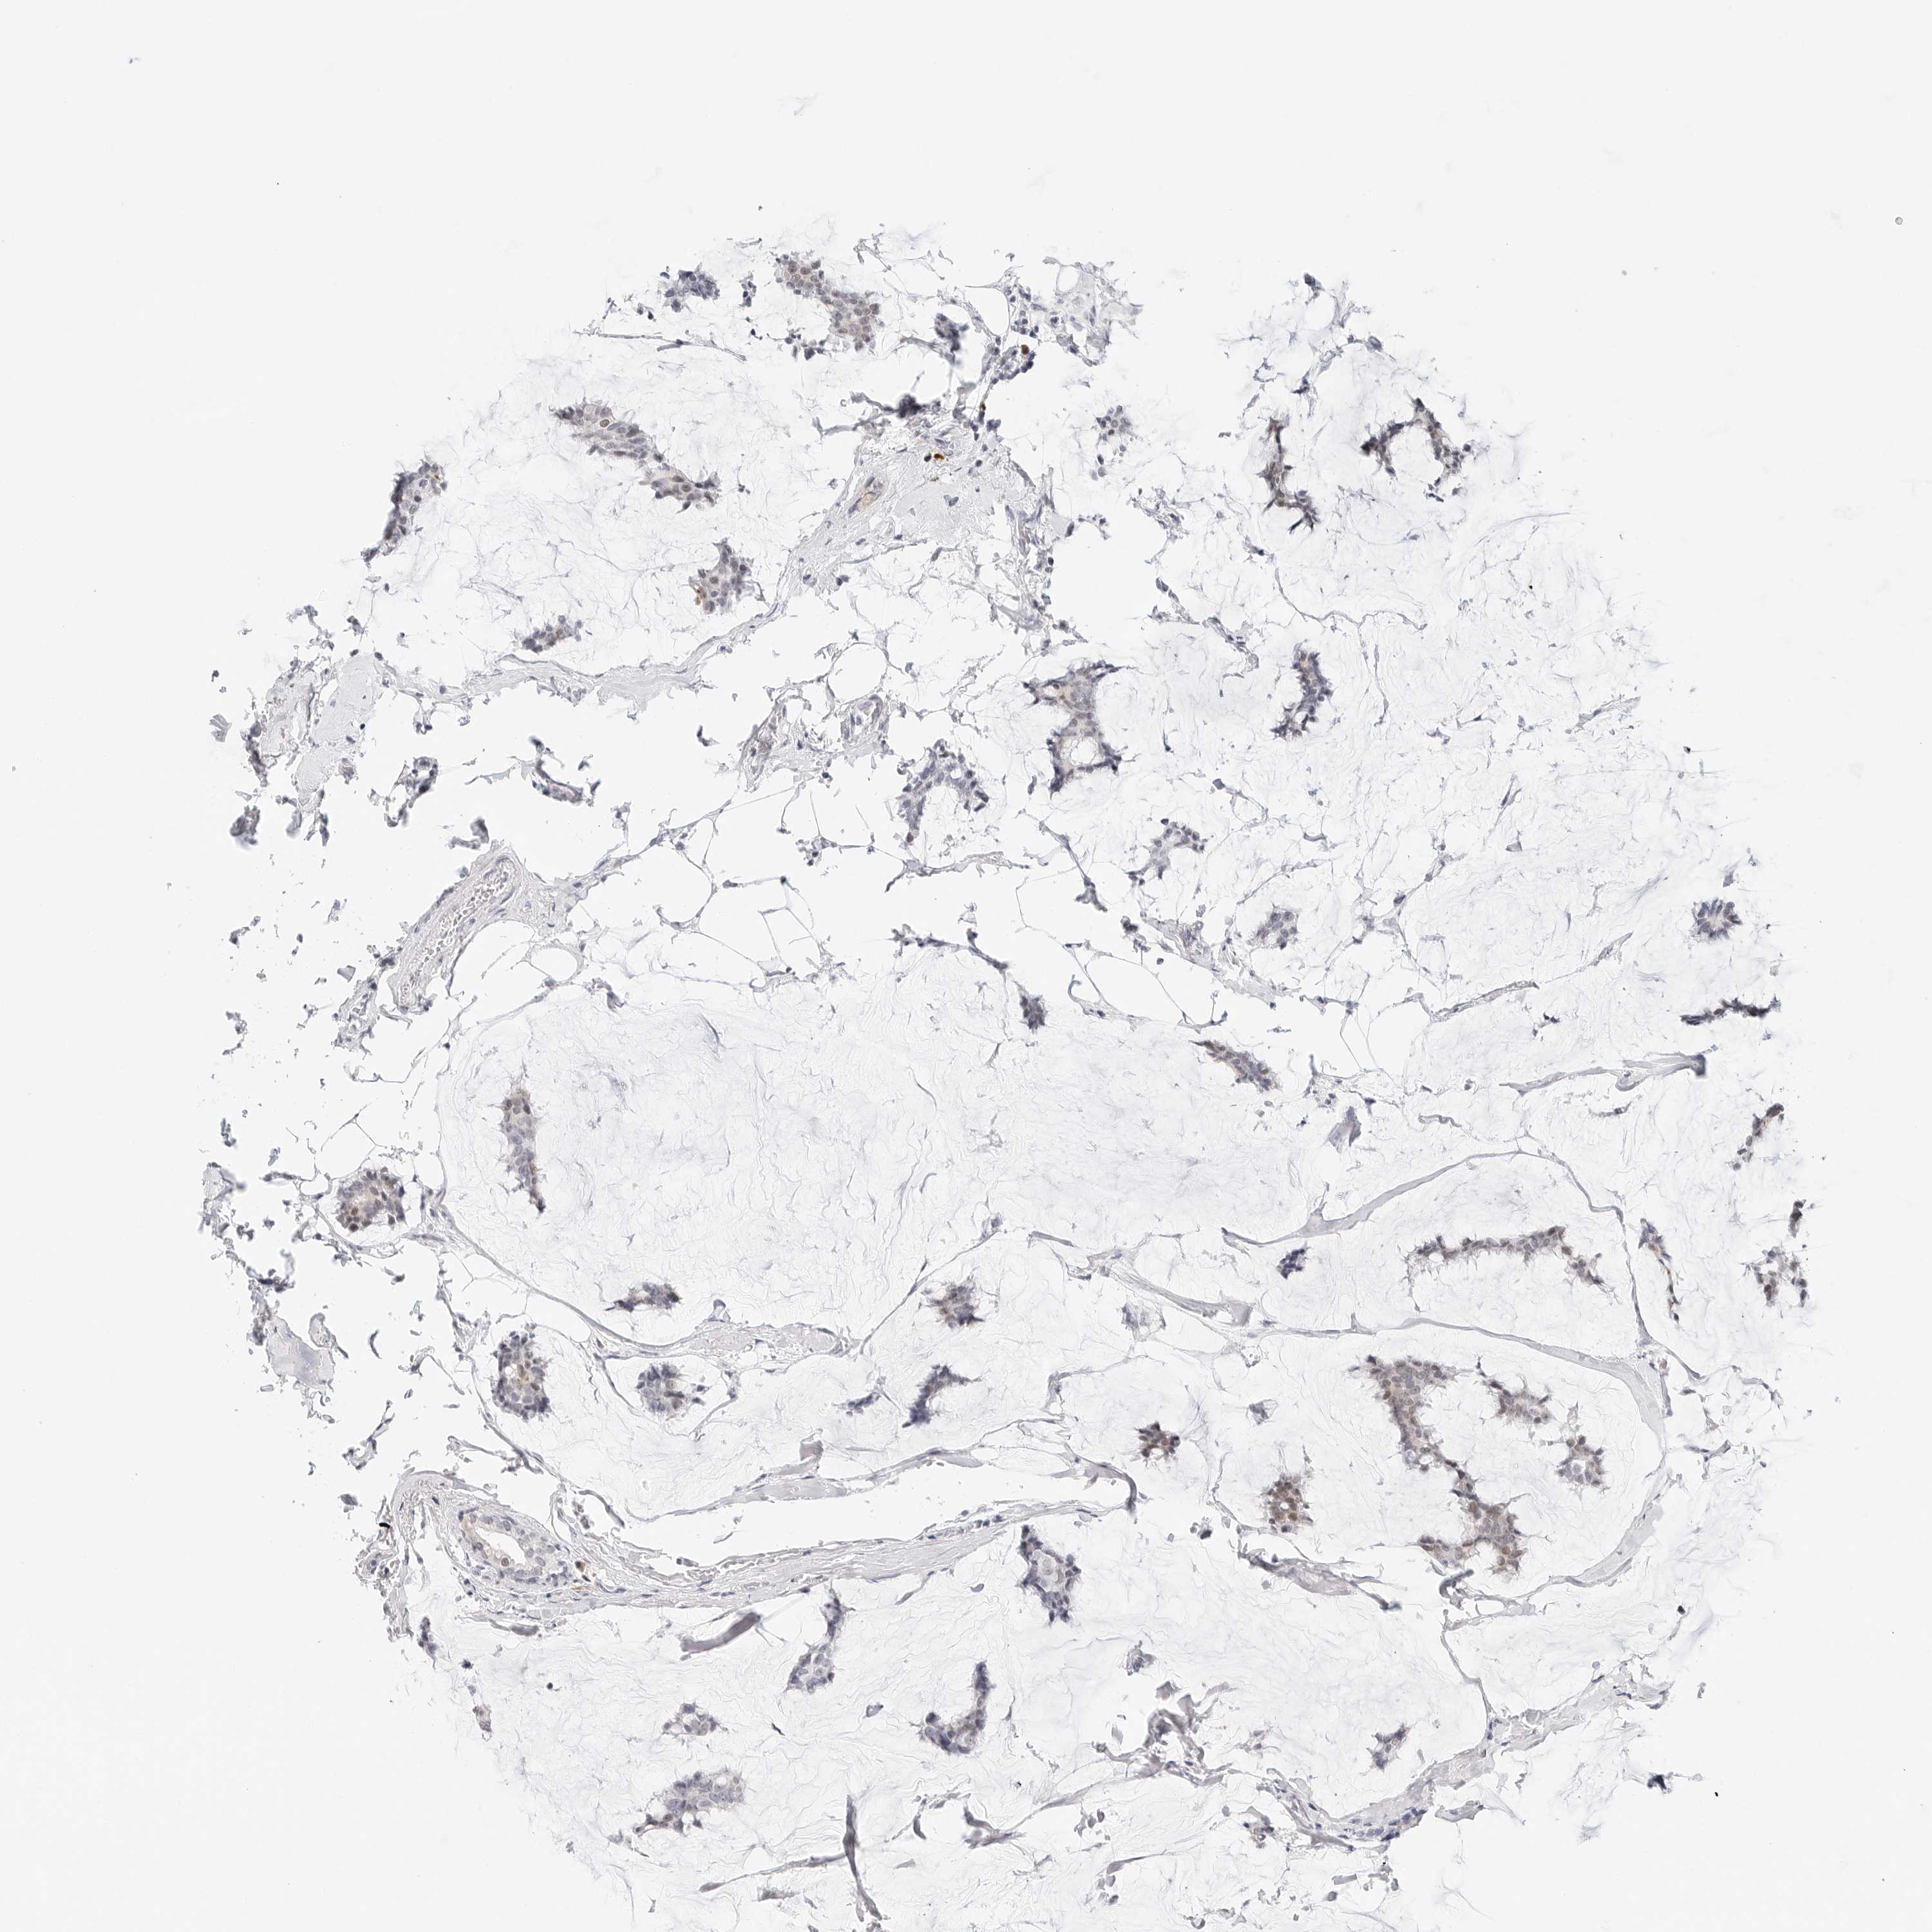

CANCER BREAST CANCER Show tissue menu

BRCA TCGA BRCA VALIDATION PROTEIN EXPRESSION